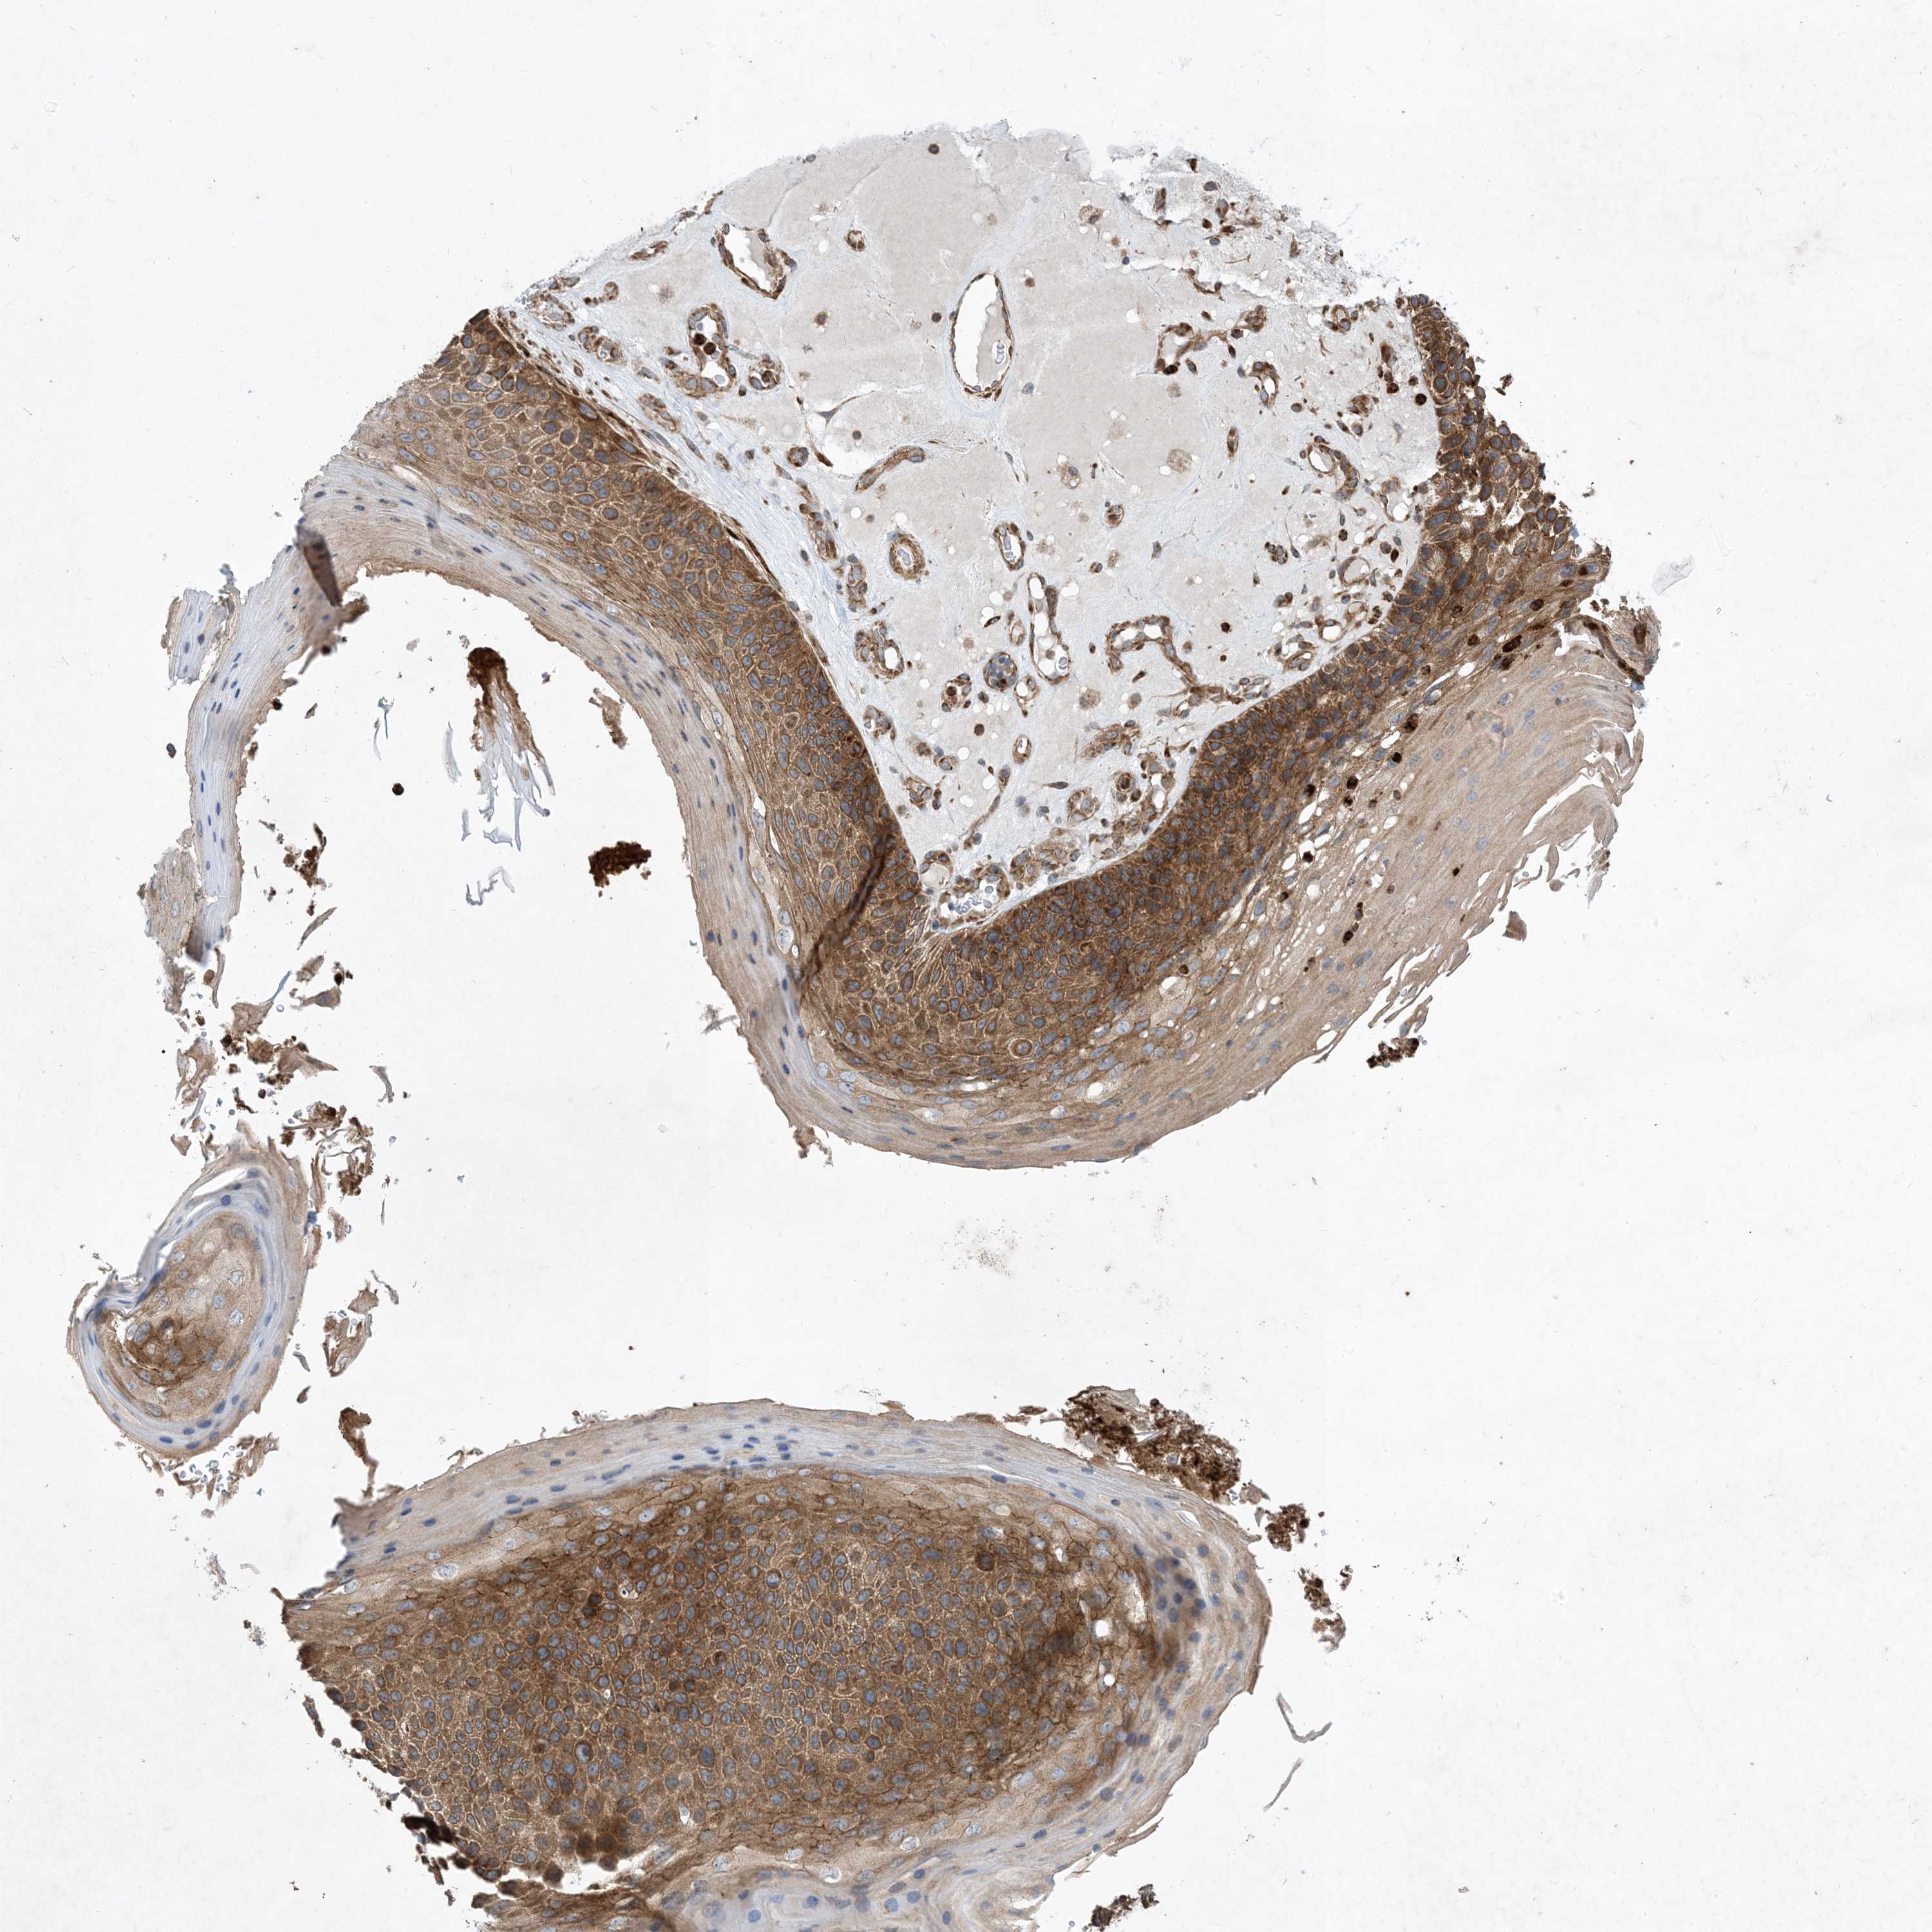

Basal cell and squamous cell cancer

SKIN CANCER - Protein expressioni

A mouse-over function shows sample information and annotation data. Click on an image to view it in a full screen mode. Samples can be filtered based on level of antibody staining by selecting one or several of the following categories: high, medium, low and not detected. The assay and annotation is described here.

Antibody stainingi

Antibody staining in the annotated cell types in the current human tissue is reported as not detected, low, medium, or high, based on conventional immunohistochemistry profiling in selected tissues. This score is based on the combination of the staining intensity and fraction of stained cells.

Each image is clickable and will lead to virtual microscopy that enables deeper exploration of all samples and also displays staining intensity scores, fraction scores and subcellular localization as well as patient and tissue information for each sample.

Antibody HPA035599

Staining

High

Intensity

Strong

Quantity

>75%

Location

Nuclear

Squamous cell carcinoma, NOS